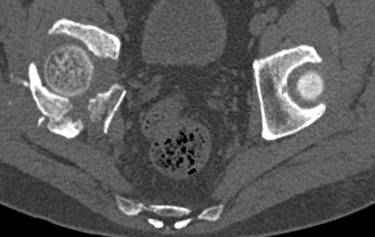

высылаю дополнительно сканы.

итак, второй вариант: высокий двухколонный с вовлечением КПС... Ни одно из основных повреждений не репонировано, кроме задней стенки. Скорее всего попытка реконструкции вертлуги сейчас будет очень травматичной и не очень эфективной, т.е. вероятный риск более значим, чем ожидаемая польза... Лучше подождать, и потом сразу эндопротез

подождать сколько, чего? такая дыра в задней колонне не закроется никогда.

потом эндопротез какой? в такой ситуации приходит на ум Burch-Schneider cage, в 35 лет, дальше что делать?